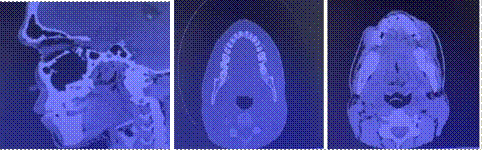

Tomografía Axial Computarizada.

A: Corte Sagital                               B- C Corte Axial

Se evidencia en los cortes axiales evaluados, configuración normal con respecto a hueso frontal, musculatura sin alteración aparente, en zona mandíbular izquierda existe la evidencia de imagen que compromete la arcada dental inferior descrita como una lesión ocupante de espacio, produciendo aumento en zonas blandas.